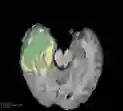

Deep neural network models used for medical image segmentation are large because they are trained with high-resolution three-dimensional (3D) images. Graphics processing units (GPUs) are widely used to accelerate the trainings. However, the memory on a GPU is not large enough to train the models. A popular approach to tackling this problem is patch-based method, which divides a large image into small patches and trains the models with these small patches. However, this method would degrade the segmentation quality if a target object spans multiple patches. In this paper, we propose a novel approach for 3D medical image segmentation that utilizes the data-swapping, which swaps out intermediate data from GPU memory to CPU memory to enlarge the effective GPU memory size, for training high-resolution 3D medical images without patching. We carefully tuned parameters in the data-swapping method to obtain the best training performance for 3D U-Net, a widely used deep neural network model for medical image segmentation. We applied our tuning to train 3D U-Net with full-size images of 192 x 192 x 192 voxels in brain tumor dataset. As a result, communication overhead, which is the most important issue, was reduced by 17.1%. Compared with the patch-based method for patches of 128 x 128 x 128 voxels, our training for full-size images achieved improvement on the mean Dice score by 4.48% and 5.32 % for detecting whole tumor sub-region and tumor core sub-region, respectively. The total training time was reduced from 164 hours to 47 hours, resulting in 3.53 times of acceleration.